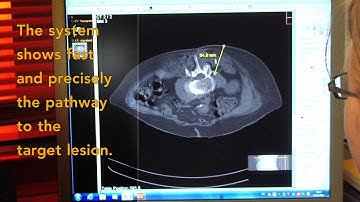

amedo Laser Navigation System for CT-guided interventions